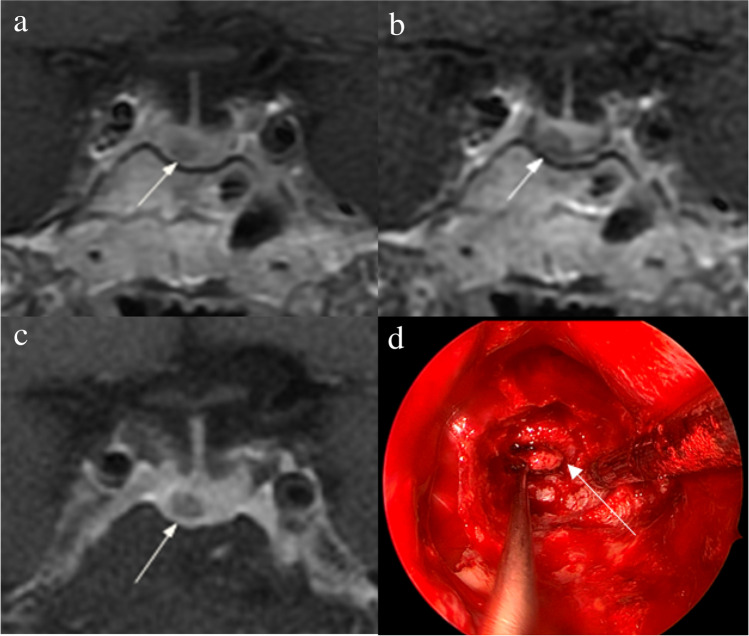

Figure 2 shows that a 5-mm pituitary microadenoma was identified on preoperative pituitary MRI. The margin of the lesion was fully delineated on hrMRI, but not on cMRI and dMRI. Figure 3 shows that a 3-mm pituitary microadenoma was missed on cMRI, but identified on dMRI and hrMRI. Figure 4 shows that a 5-mm pituitary microadenoma was correctly diagnosed on hrMRI, but missed on cMRI or dMRI. Figure 5 shows that a 4-mm pituitary microadenoma was evident on coronal images as well as reconstructed axial and reconstructed sagittal images on hrMRI.

Fig. 2.

Images in a 56-year-old man with Cushing’s disease. The 5-mm pituitary microadenoma (arrow) can be identified on (a) coronal contrast-enhanced T1-weighted image and (b) coronal dynamic contrast-enhanced T1-weighted image obtained with two-dimensional (2D) fast spin echo (FSE) sequence, but the margin is not fully delineated. The lesion (arrow) is well delineated on (c) coronal contrast-enhanced T1-weighted image on high-resolution MRI obtained with 3D FSE sequence. d Intraoperative endoscopic photograph during transsphenoidal surgery after exposure of the sellar floor shows a round pituitary microadenoma (arrow)